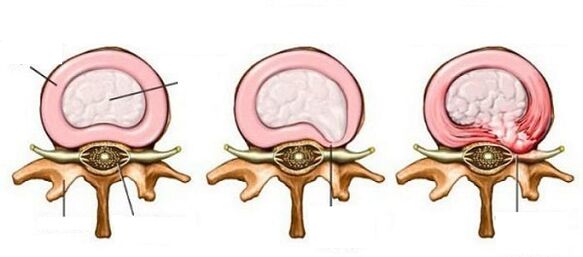

Ang proseso ng pag -unlad ng sakit

Ang Osteochondrosis ng cervical spine, bago pumasok sa isang matinding form na nangangailangan ng interbensyon sa kirurhiko, ay pumasa sa tatlong yugto:

- Ang istraktura ng pulpoic disk nucleus ay nasira. Nangyayari ito sa panahon ng pag -aalis ng tubig, pagpapatayo, pagbawas. Kapag ang disk ay nagiging mas payat, hindi na ito makayanan ang mga naglo -load. Ang unang yugto ng sakit ay hindi nagiging sanhi ng matinding sakit, dahil sa kung saan kakaunti ang mga tao na makipag -ugnay sa doktor sa oras.

- Ang fibrous singsing ng disk ay nagiging mas payat, ang disc mismo ay lumalawak, ay lilitaw na lampas sa mga gilid ng vertebra, pagkatapos kung saan nangyayari ang isang matinding sakit na sindrom.

- Dahil sa pagpapapangit ng fibrous singsing, ang mga nucleus ay nagmumula, na bumubuo ng isang hernia na nakakaantig sa mga kalamnan, arterya, nagbabago ang istraktura ng vertebrae, binabawasan ang sirkulasyon ng dugo ng cerebellum.